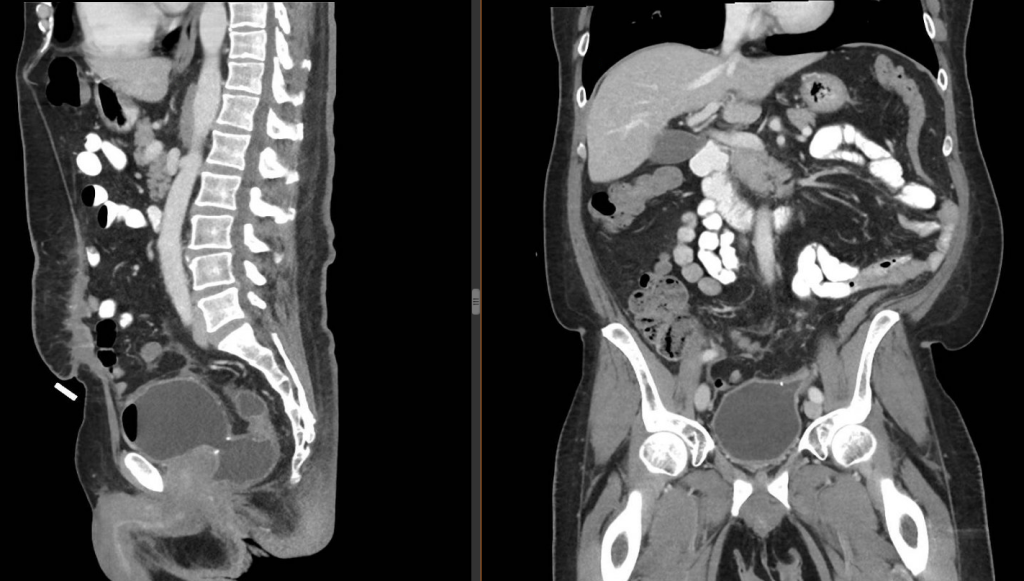

Sagittal view of rectovesicular fistula (left) with noted staples at fistula site and direct communication from mid-rectum to bladder. (Right) Coronal view of more proximal colovesicular fistula with staples noted to the left lateral aspect of the dome of the bladder connecting to the distal descending colon.

Pictured is the proposed mechanism of injury to explain the iatrogenic creation of both a colovesicular fistula and rectovesicular fistula. The End-to-End Anastomosis (EEA) stapler within the rectal stump is​thought to have deployed the stapler shaft anteriorly through the rectal stump, including the caudal and cephalad portion of the decompressed bladder at the time of the Hartmann's reversal. This proposed mechanism would still allow the shaft of the EEA to mate with the anvil within the distal descending colon with inclusion of the bladder within the anastomosis.